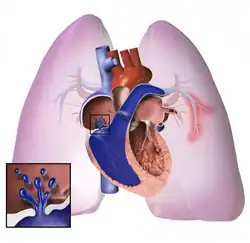

The pathogenesis of pulmonary arterial hypertension (WHO Group I) involves the narrowing of blood vessels connected to and within the lungs. This makes it harder for the heart to pump blood through the lungs, as it is much harder to make water flow through a narrow pipe as opposed to a wide one. Over time, the affected blood vessels become stiffer and thicker, in a process known as fibrosis. The mechanisms involved in this narrowing process include vasoconstriction, thrombosis, and vascular remodeling (excessive cellular proliferation, fibrosis, and reduced apoptosis/programmed cell death in the vessel walls, caused by inflammation, disordered metabolism and dysregulation of certain growth factors).[27][28] This further increases the blood pressure within the lungs and impairs their blood flow. In common with other types of pulmonary hypertension, these changes result in an increased workload for the right side of the heart.[16][29] The right ventricle is normally part of a low pressure system, with systolic ventricular pressures that are lower than those that the left ventricle normally encounters. As such, the right ventricle cannot cope as well with higher pressures, and although right ventricular adaptations (hypertrophy and increased contractility of the heart muscle) initially help to preserve stroke volume, ultimately these compensatory mechanisms are insufficient; the right ventricular muscle cannot get enough oxygen to meet its needs and right heart failure follows.[16][28][29] As the blood flowing through the lungs decreases, the left side of the heart receives less blood. This blood may also carry less oxygen than normal. Therefore, it becomes harder and harder for the left side of the heart to supply sufficient oxygen to the rest of the body, especially during physical activity.[30][31][11] During the end-systolic volume phase of the cardiac cycle, the Gaussian curvature and the mean curvature of the right ventricular endocardial wall of PH patients were found to be significantly different as compared to controls.[32]

Pathogenesis in pulmonary hypertension due to left heart disease (WHO Group II) is completely different in that constriction or damage to the pulmonary blood vessels is not the issue. Instead, the left heart fails to pump blood efficiently, leading to pooling of blood in the lungs and back pressure within the pulmonary system. This causes pulmonary edema and pleural effusions.[35] In the absence of pulmonary blood vessel narrowing, the increased back pressure is described as 'isolated post-capillary pulmonary hypertension' (older terms include 'passive' or 'proportionate' pulmonary hypertension or 'pulmonary venous hypertension'). However, in some patients, the raised pressure in the pulmonary vessels triggers a superimposed component of vessel narrowing, which further increases the workload of the right side of the heart. This is referred to as 'post-capillary pulmonary hypertension with a pre-capillary component' or 'combined post-capillary and pre-capillary pulmonary hypertension' (older terms include 'reactive' or 'out-of-proportion' pulmonary hypertension).[13][18][36]

In pulmonary hypertension due to lung diseases and/or hypoxia (WHO Group III), low levels of oxygen in the alveoli (due to respiratory disease or living at high altitude) cause constriction of the pulmonary arteries. This phenomenon is called hypoxic pulmonary vasoconstriction, and it is initially a protective response to stop too much blood from flowing to areas of the lung that are damaged and do not contain oxygen. When the alveolar hypoxia is widespread and prolonged, this hypoxia-mediated vasoconstriction occurs across a large portion of the pulmonary vascular bed and leads to an increase in pulmonary arterial pressure, with thickening of the pulmonary vessel walls contributing to the development of sustained pulmonary hypertension.[11][37][38][39] Prolonged hypoxia also induces the transcription factor HIF1A, which directly activates downstream growth factor signaling that causes irreversible proliferation and remodeling of pulmonary arterial endothelial cells, leading to chronic pulmonary arterial hypertension.

In chronic thromboembolic pulmonary hypertension, or CTEPH (WHO Group IV), the initiating event is thought to be blockage or narrowing of the pulmonary blood vessels with unresolved blood clots; these clots can lead to increased pressure and shear stress in the rest of the pulmonary circulation, precipitating structural changes in the vessel walls (remodeling) similar to those observed in other types of severe pulmonary hypertension. This combination of vessel occlusion and vascular remodeling once again increases the resistance to blood flow, and so the pressure within the system rises.[40][41]